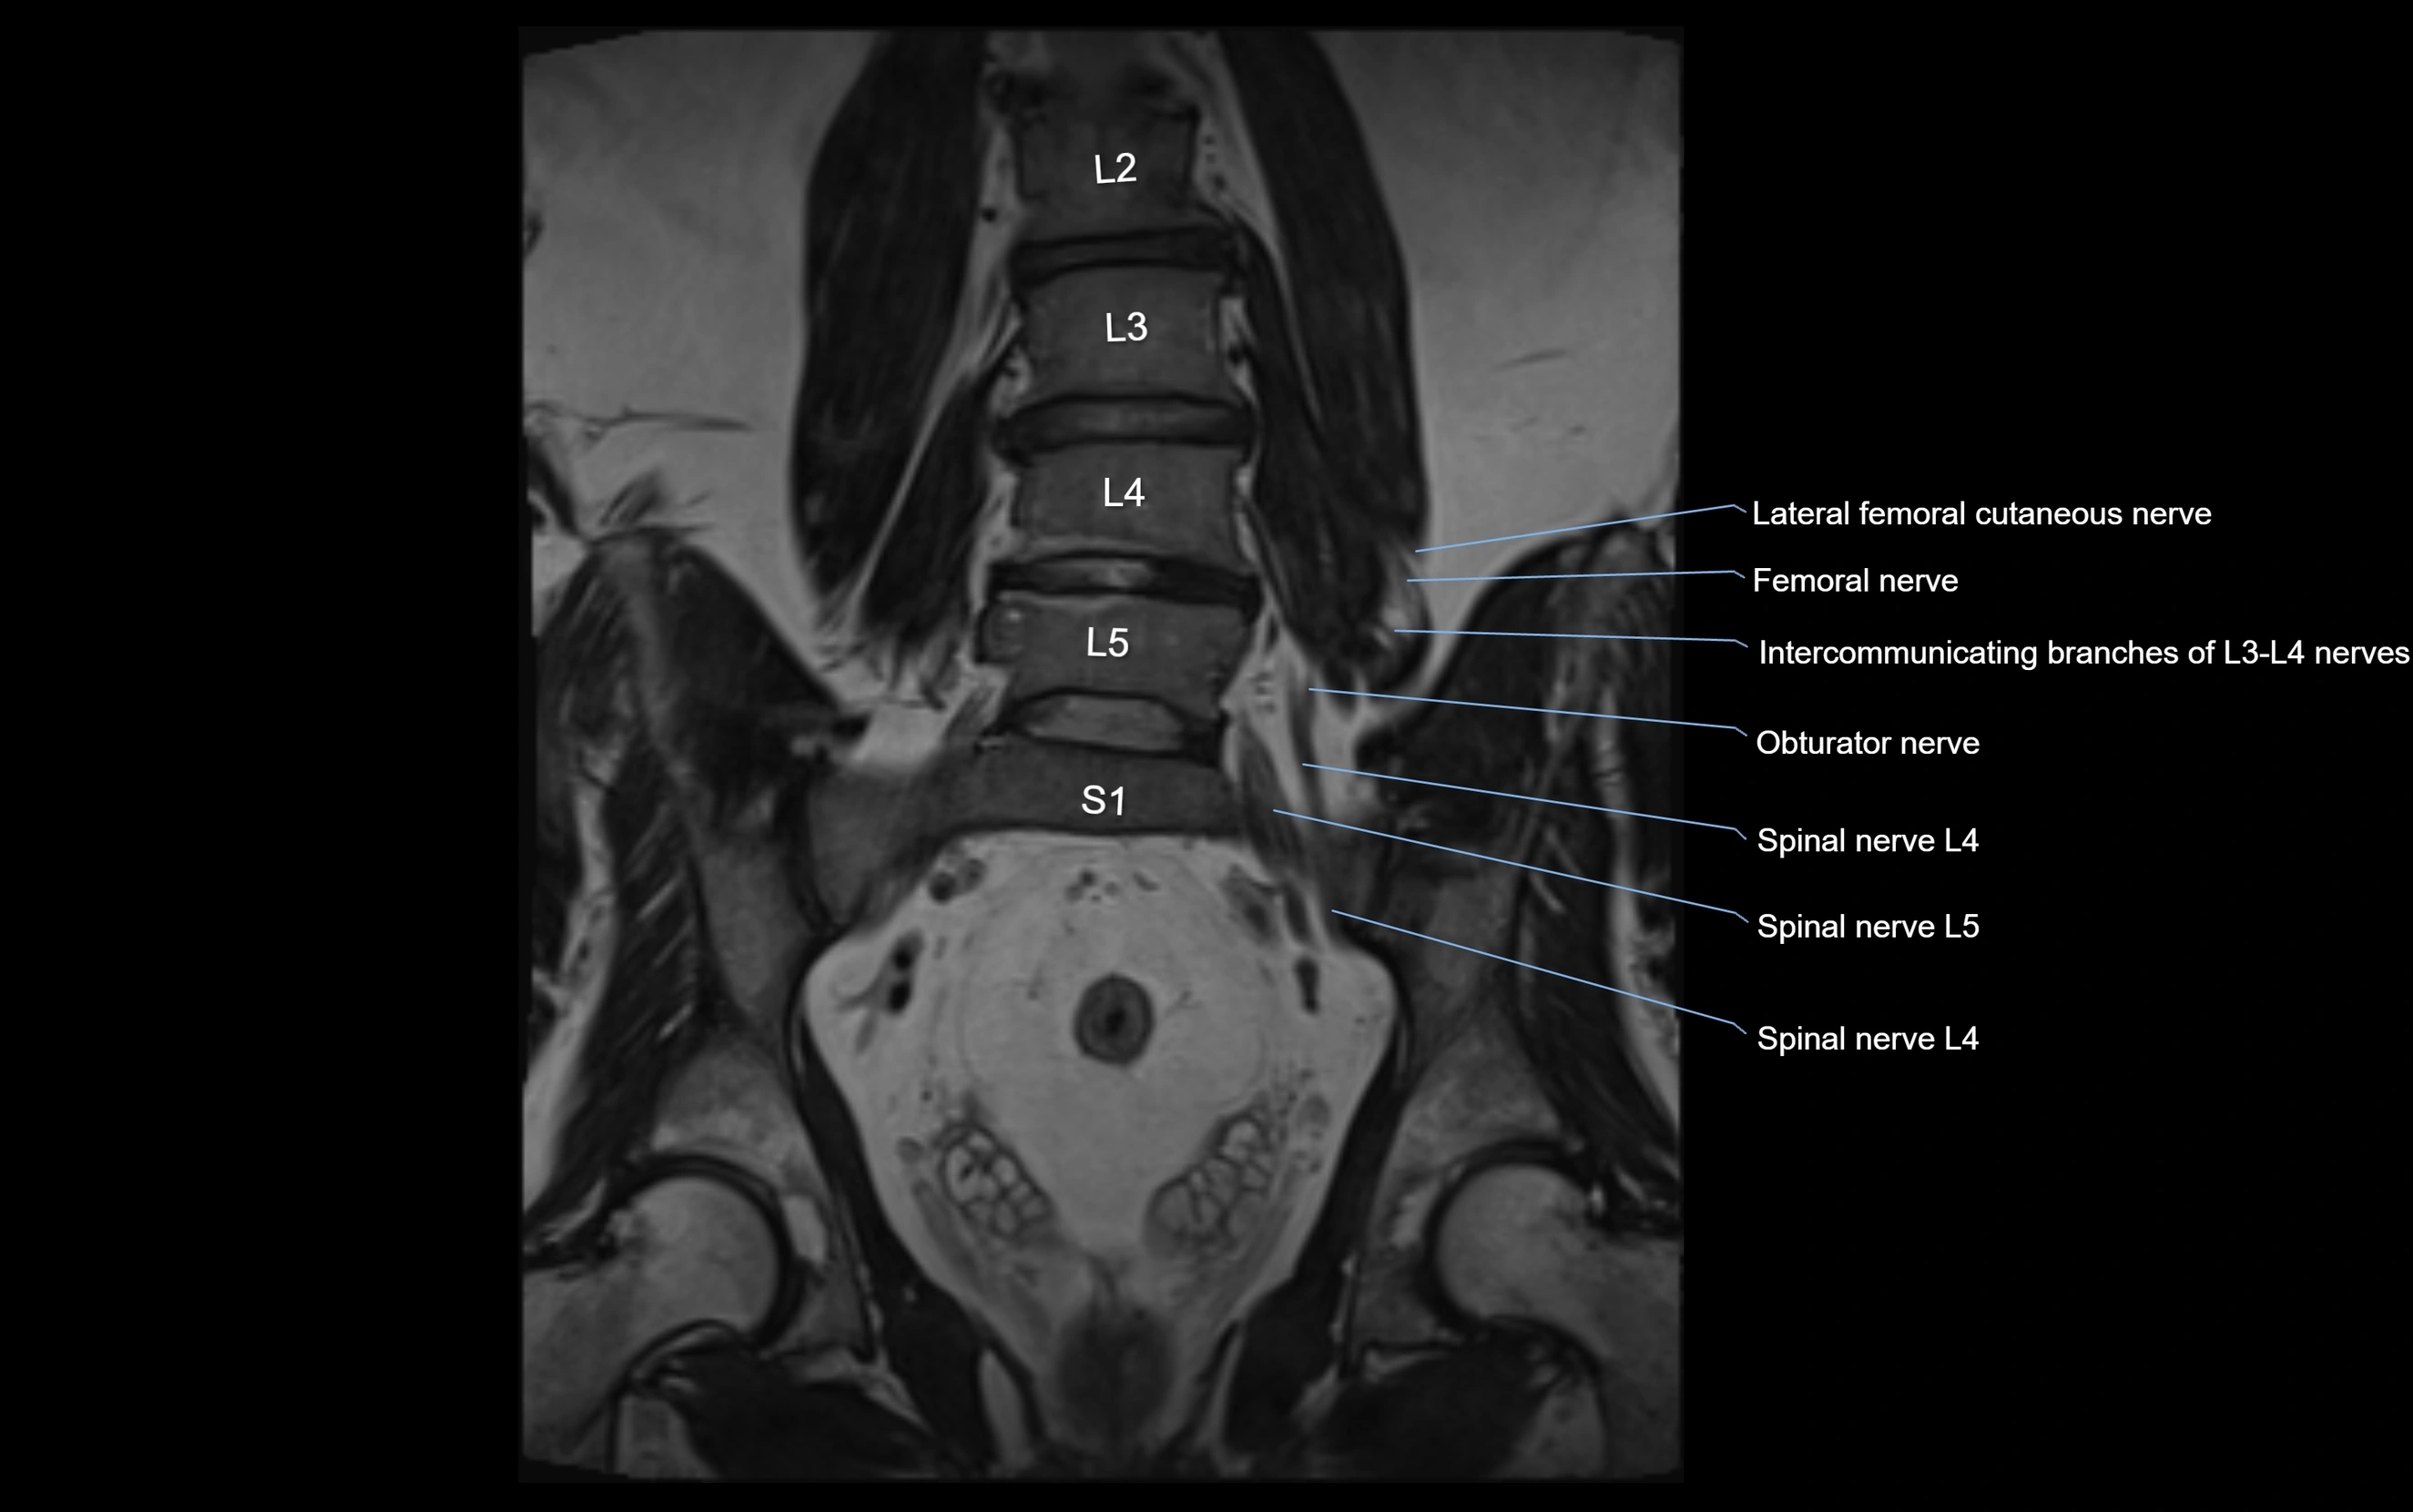

MRI image

image